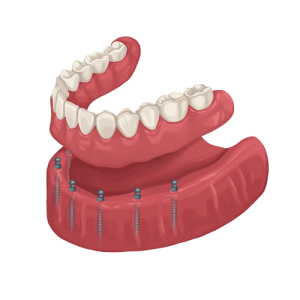

Dental Implant Overdenture

For patients who are edentulous and missing all of their teeth, an implant supported denture may be a viable solution as well, this procedure replaces all missing teeth by utilising a couple of implants to retain or support a denture.

Since dental implants are inserted directly into the jawbone, implant retained/supported dentures are a lot comfortable than regular dentures and almost immovable, making biting and chewing feel as natural as possible.

Dental Implant Overdenture

For patients who are edentulous and missing all of their teeth, an implant supported denture may be a viable solution as well, this procedure replaces all missing teeth by utilising a couple of implants to retain or support a denture.

Since dental implants are inserted directly into the jawbone, implant retained/supported dentures are a lot comfortable than regular dentures and almost immovable, making biting and chewing feel as natural as possible.